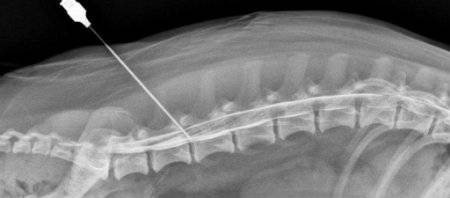

- Процедура проводится под рентгенологическим контролем.

Врач вводит лекарство с помощью иглы, продвигая ее между позвонков. Когда при отсасывании жидкости появляется кровь, игла продвигается в том же направлении. При появлении в шприце спинномозговой жидкости процедура прерывается. После прохождения на глубину 50 мм начинается введение медикаментозного средства, на этом этапе у больного возникает неприятное ощущение в зоне пораженного отдела. Во время одной блокады вводится 30-60мл лекарства.